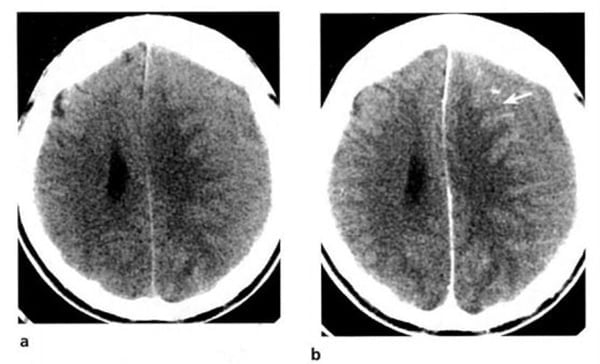

2.2. Nhồi máu não (Hình 1.40, 1.41)

Dấu hiệu XQCTĐT:

– Từ 12 đến 48 giờ: vùng mật độ thấp mơ hồ, giới hạn không rõ, hiệu ứng choán chỗ nhẹ (xóa rãnh vỏ, di lệch não thất nếu nhồi máu rộng). Không bắt chất cản quang thường xuyên. Xuất huyết xảy ra trong 5-10% với mật độ cao tự nhiên.

– Từ 48 đến 96 giờ: khối choán chỗ tăng dần. Vùng khu trú hình tam giác hoặc hình V, mật độ thấp, ảnh hưởng vỏ não và chất trắng dưới vỏ cho đến bề mặt não thất.

– Từ 4 đến 7 ngày: xuất hiện bắt chất cản quang dạng hồi não và có thể tồn tại trong 8 tuần. Nhồi máu mật độ thấp, phù bao quanh có mật độ thấp hơn.

– Từ 2 đến 8 tuần: hiệu ứng choán chỗ giảm dần, có thể còn bắt chất cản quang.

– Nhồi máu cũ: vùng mật độ thấp, giới hạn rõ, giãn nở não thất và rãnh vỏ lân cận. Hiếm đóng vôi.

Hình 1.41. Nhồi máu não ở tay sau của bao trong bên phải. Vài giờ sau khi xuất hiện triệu chứng của đột quỵ. XQCLĐT (a) âm tính. Sáu ngày sau (b), tổn thương mật độ thấp hiện rõ. Do kích thước nhỏ, hiệu ứng choán chỗ không đáng kể.